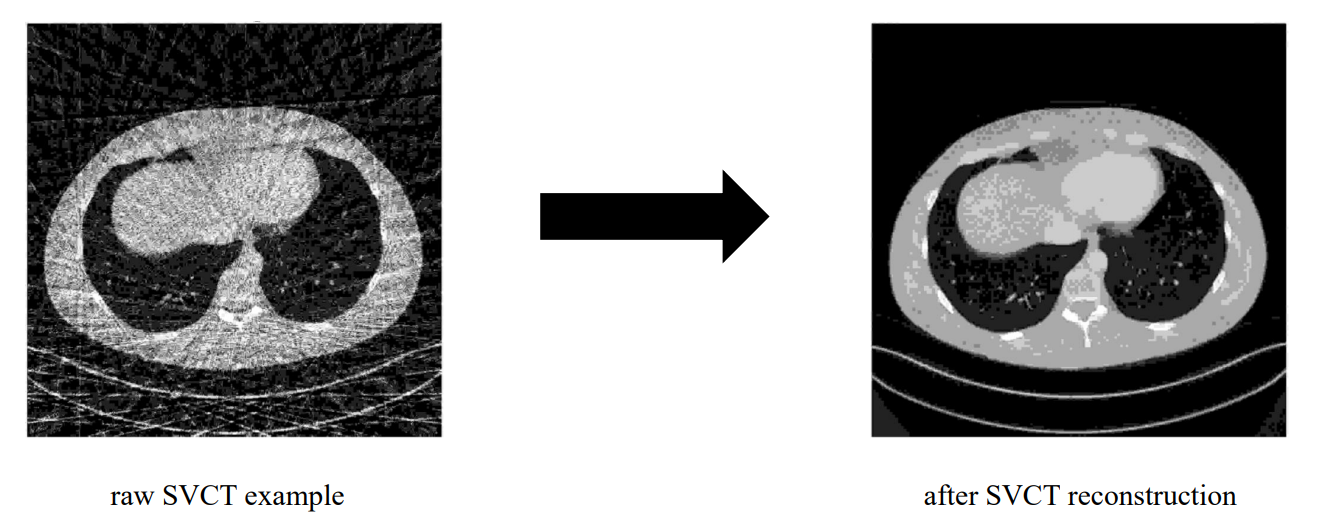

그렇다면 SVCT는 무엇일까요? 우선 SVCT는 Sparse(드문, 희박한) View CT의 약자입니다.

하지만 projection을 많이 얻는다는 것은 환자에게 그만큼 많은 양의 방사선을 조사한다는 뜻입니다. SVCT는 일반 CT에 비해 촬영 각도의 간격이 훨씬 큽니다. 즉 sinogram을 구성하는 projection들의 수가 훨씬 적은 것이죠. 방사선 조사량을 줄일 수 있지만, 위 그림처럼 SVCT의 sinogram은 일반 CT의 sinogram보다 정보량이 빈약합니다. 그 결과로 위 그림의 오른쪽과 같은 뭔가 이상한 SVCT 사진을 얻게 됩니다.

그런 SVCT를 일반 CT처럼 복원하는 연구 주제가 SVCT reconstruction입니다.